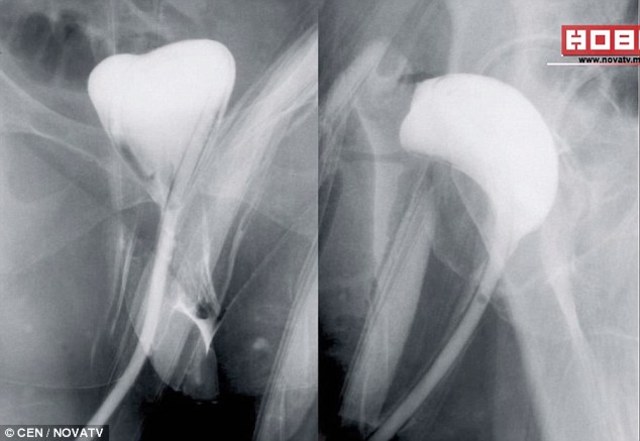

據《每日郵報》報導,Jasminka因罹患結腸癌。3年前她在馬其頓首都史高比耶一間醫院進行切除腫瘤手術。手術後醫生問她有否放屁,她說有但氣體從陰道排出。當時醫生說沒有任何問題,但Jasminka就很害怕。之後院方替她照X光,發現Jasminka的結腸竟與陰道連接起來。更誇張的是Jasminka的結腸腫瘤仍在,根本沒有切除。導致Jasminka需要再接受手術切除腫瘤,不過她不信任出問題的這間醫院,決定在另一間醫院進行手術,挨了兩次刀。(圖片來源/每日郵報)